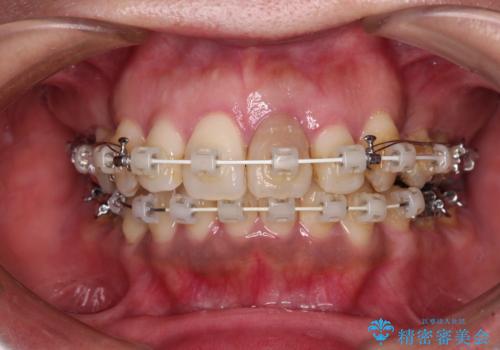

- 矯正装置

- 審美装置

- 歯列全体が内側に倒れ込んでいることと、口元の突出感を気にして来院された患者様です。

上下ともに歯列が狭窄しており、前方に突出している状態でした。

歯が重なるような叢生も認められたため、上下左右の第一小臼歯4本を抜歯して、口元が引っ込むように治療を行うこととしました。

口元を引っ込めることができたため、口を閉じるときに力が入っていて皺のよっていた顎先も、スムーズに閉じられるようになったことで力がかからなくなりました。

変色して気になっていた前歯も、オールセラミッククラウンで自然な色合いにすることができました。